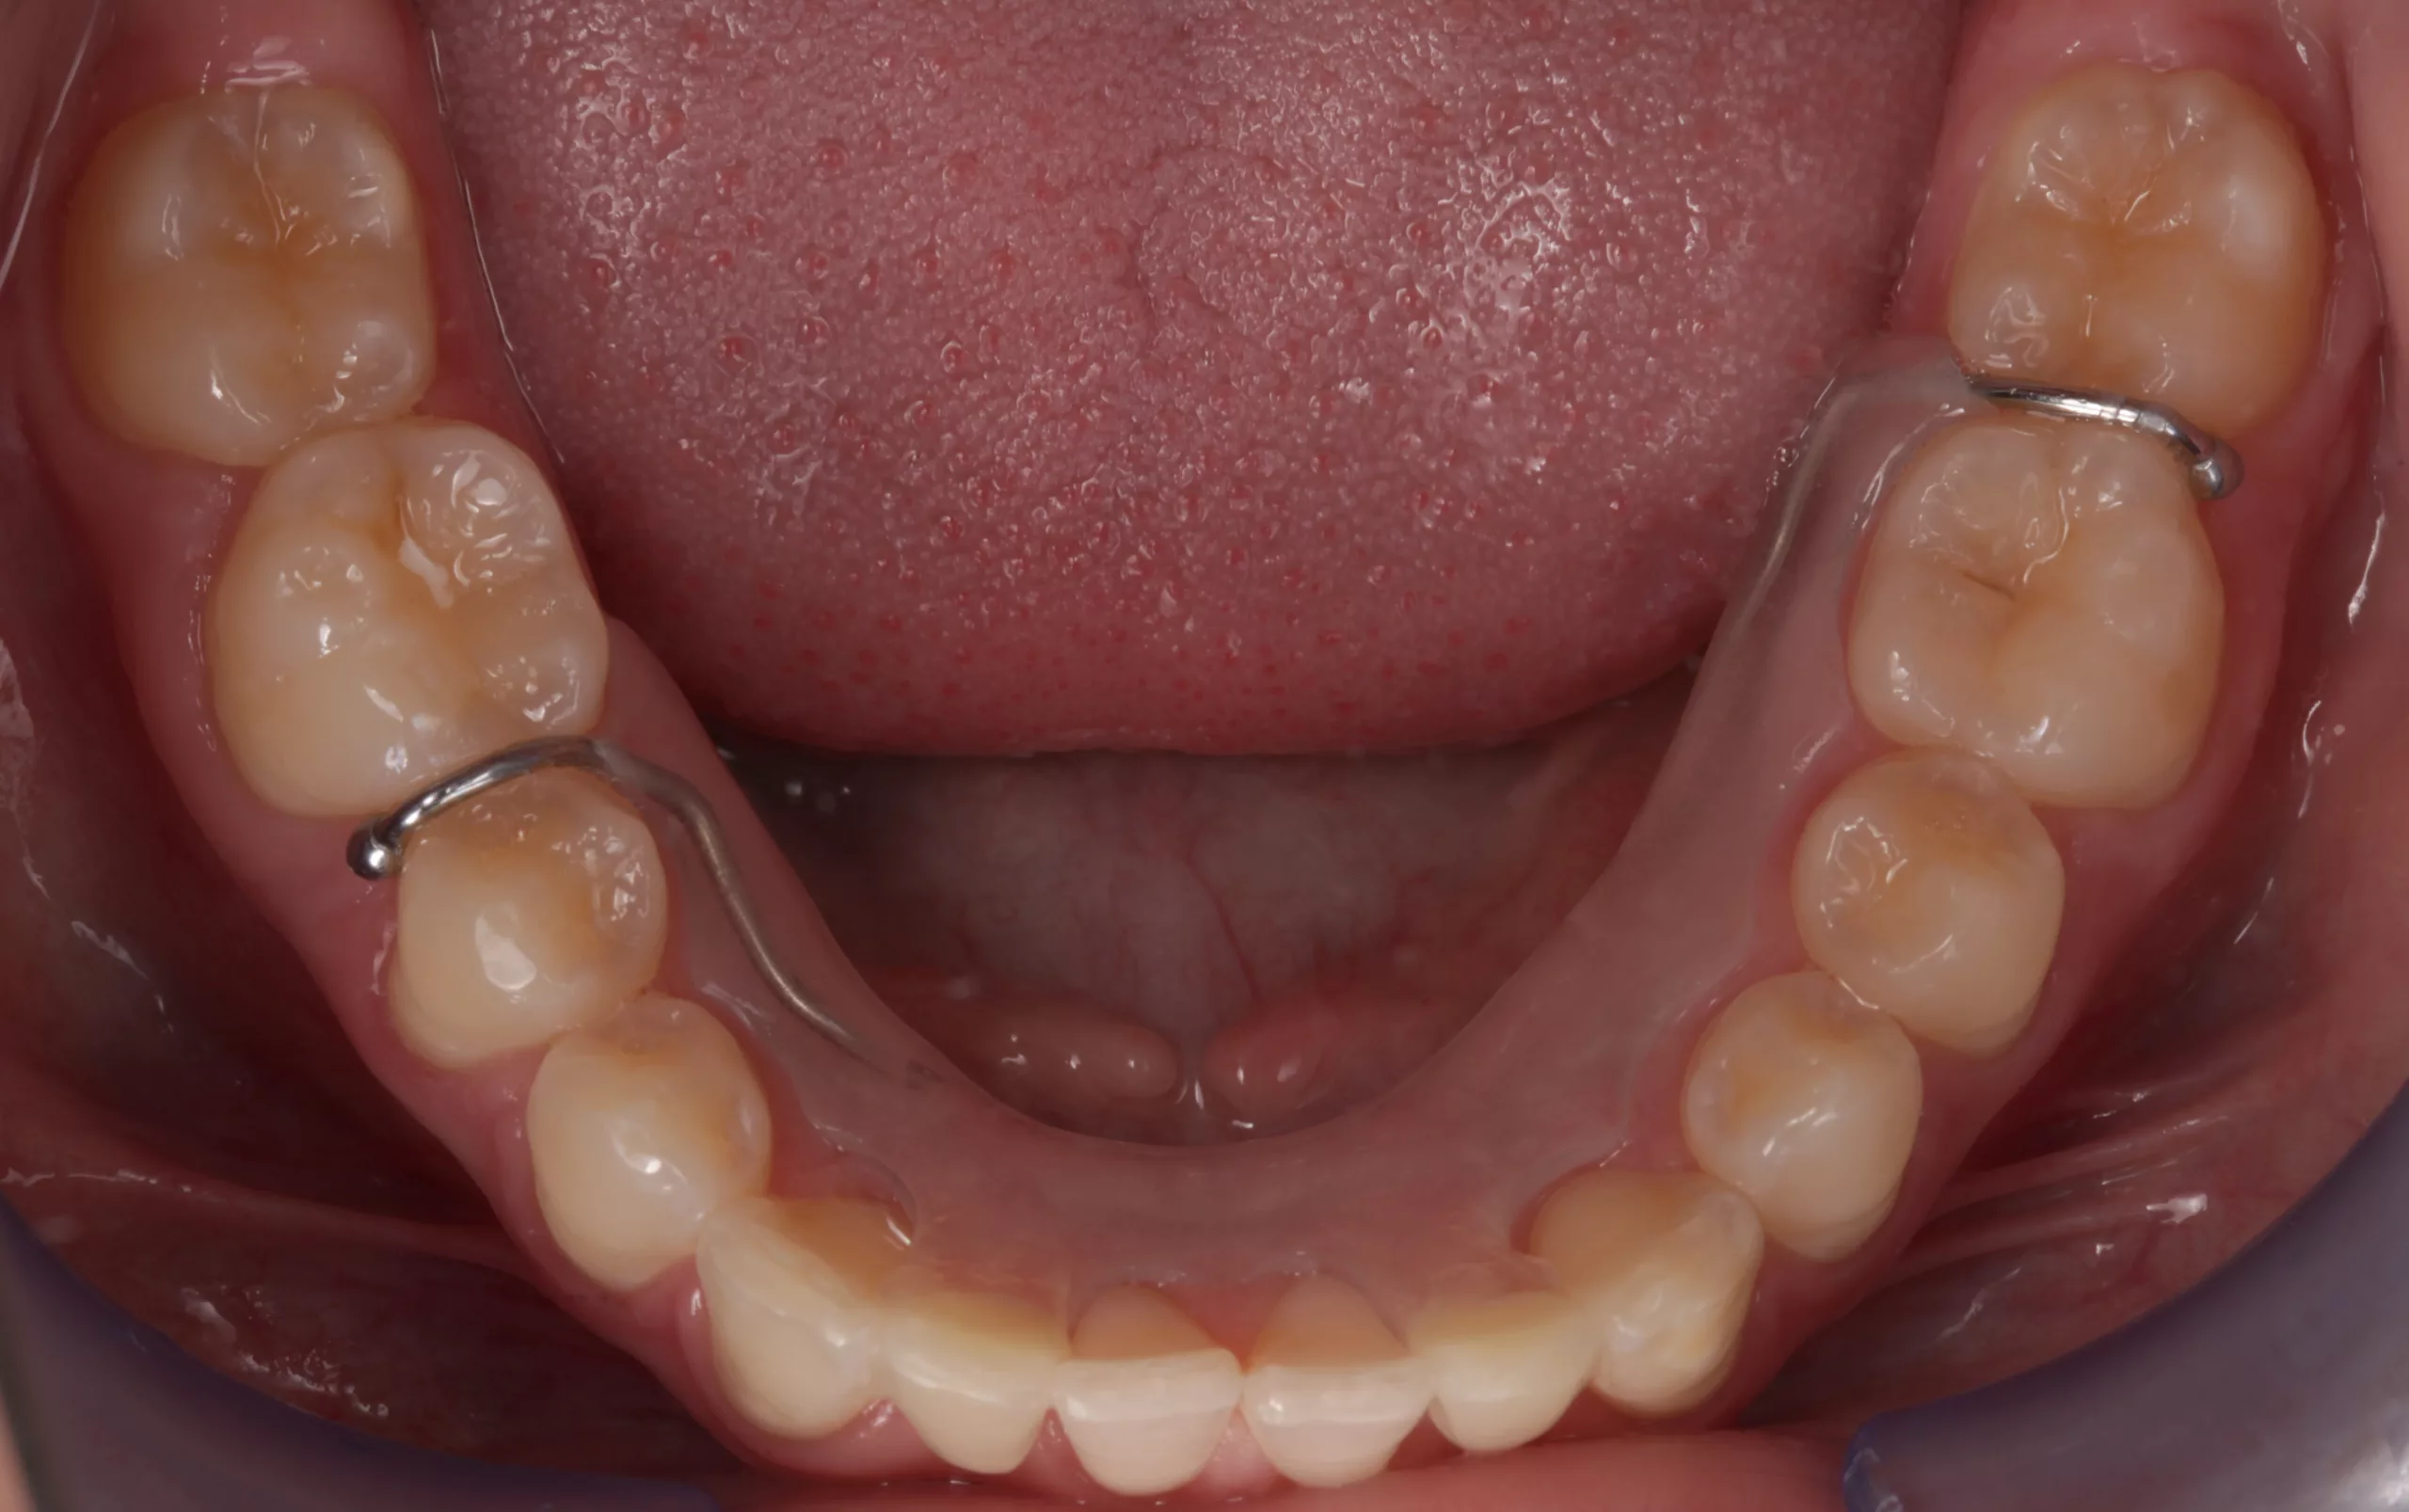

Eine 17-jährige Patientin stellte sich nach kieferorthopädischer Vorbehandlung alio loco und bereits erfolgter Lückenöffnung regio 32, 42 bei Nichtanlage 31, 41 in der Klinik für Zahnärztliche Prothetik und Biomaterialien, Zentrum für Implantologie des Universitätsklinikums Aachen mit dem Wunsch nach einer Lückenversorgung vor (Abb. 2-4). Die Lücken wurden mithilfe eines herausnehmbaren Zahnersatzes (Interimsprothese) offen gehalten. Nach aktiv- kieferorthopädischer Therapie sollten mindestens 6 bis 8 Wochen als Retentionszeit vor der definitiven, festsitzenden prothetischen Versorgung kalkuliert werden [7].

Aufgrund reduzierter Platzverhältnisse in mesiodistaler Ausdehnung musste bei der hier vorgestellten Patientin von einer implantatgetragenen Lösung Abstand genommen werden (Abb. 5). Die absolute Unversehrtheit der lückenbegrenzenden Zähne sprach zudem für eine zahnsubstanzschonende prothetische Rehabilitation. Somit fiel die Entscheidung zur Versorgung der Schaltlücken auf zwei einflügelige Adhäsivbrücken.